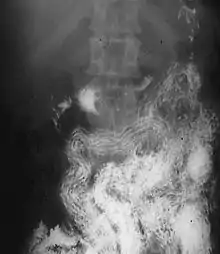

Ascaris worms (one type of helminth) in the small bowel of an infected person (X-ray image with barium as contrast medium)

Helminthiasis, also known as worm infection, is any macroparasitic disease of humans and other animals in which a part of the body is infected with parasitic worms, known as helminths. There are numerous species of these parasites, which are broadly classified into tapeworms, flukes, and roundworms. They often live in the gastrointestinal tract of their hosts, but they may also burrow into other organs, where they induce physiological damage.